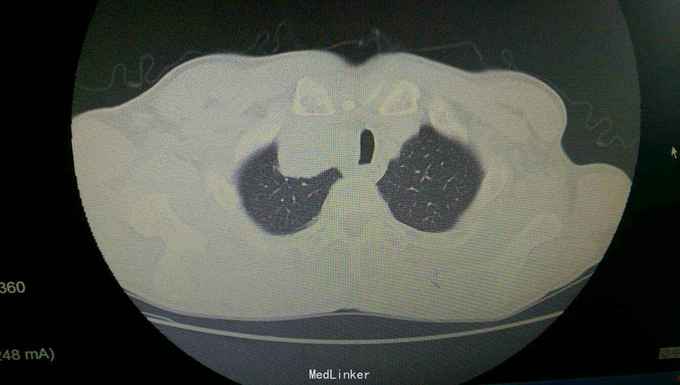

患者入院后,拟行左颌下肿块切除,在术前检查,术前准备时,常规胸片发现右侧肺部肿块,进一步行颈部及胸部ct检查,提示左颌下淋巴结肿大,转移性可能。右下肺周围性肺癌伴右肺门及纵膈多发淋巴转移考虑。决定先行左颌下肿块切除,明确诊断。术后病理示:左(左颌下腺)淋巴结转移性癌,来源首先考虑为肺。患者及家属考虑为晚期肿瘤,拒绝进一步手术治疗及化疗,下颌部切口愈合拆线后,出院。

患者出院后,门诊服中药治疗,定期复查。 讨论:患者因左颌下肿块前来就诊,术前检查发现肺部肿块,一元论考虑,应为肺部肿瘤转移所致。而且手术后病理亦证实。关键当下颌部出现肿块,应考虑肿块性质的鉴别。1.应考虑颌下肿块与颈部淋巴结的鉴别,尤其是无痛性肿块,要和淋巴结核及肿瘤等鉴别。2要和周围组织的肿瘤如甲状腺,鼻咽癌等浸润转移鉴别。3.要考虑纵膈,肺等远处转移。该患者为右下肺肿瘤已向纵膈及颈部,颌下转移,但患者临床表现仅有左颌下肿块,无胸闷气急,无咳嗽咳痰,虽ct检查发现纵膈及颈部多发淋巴结肿大,患者却无上腔静脉回流受阻,颈部浅表淋巴结未能扪及。该病例提示我们,当患者颈部出现肿块,应仔细检查,多些鉴别,以免漏诊。